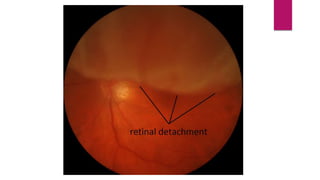

Retinal detachment

DISC

The disc appears normal.

RETINA

Observation of the retina shows a gray elevation in the

temporal area with folds in the detached section.

VESSELS

The vessels are totuous and elevated over the detached